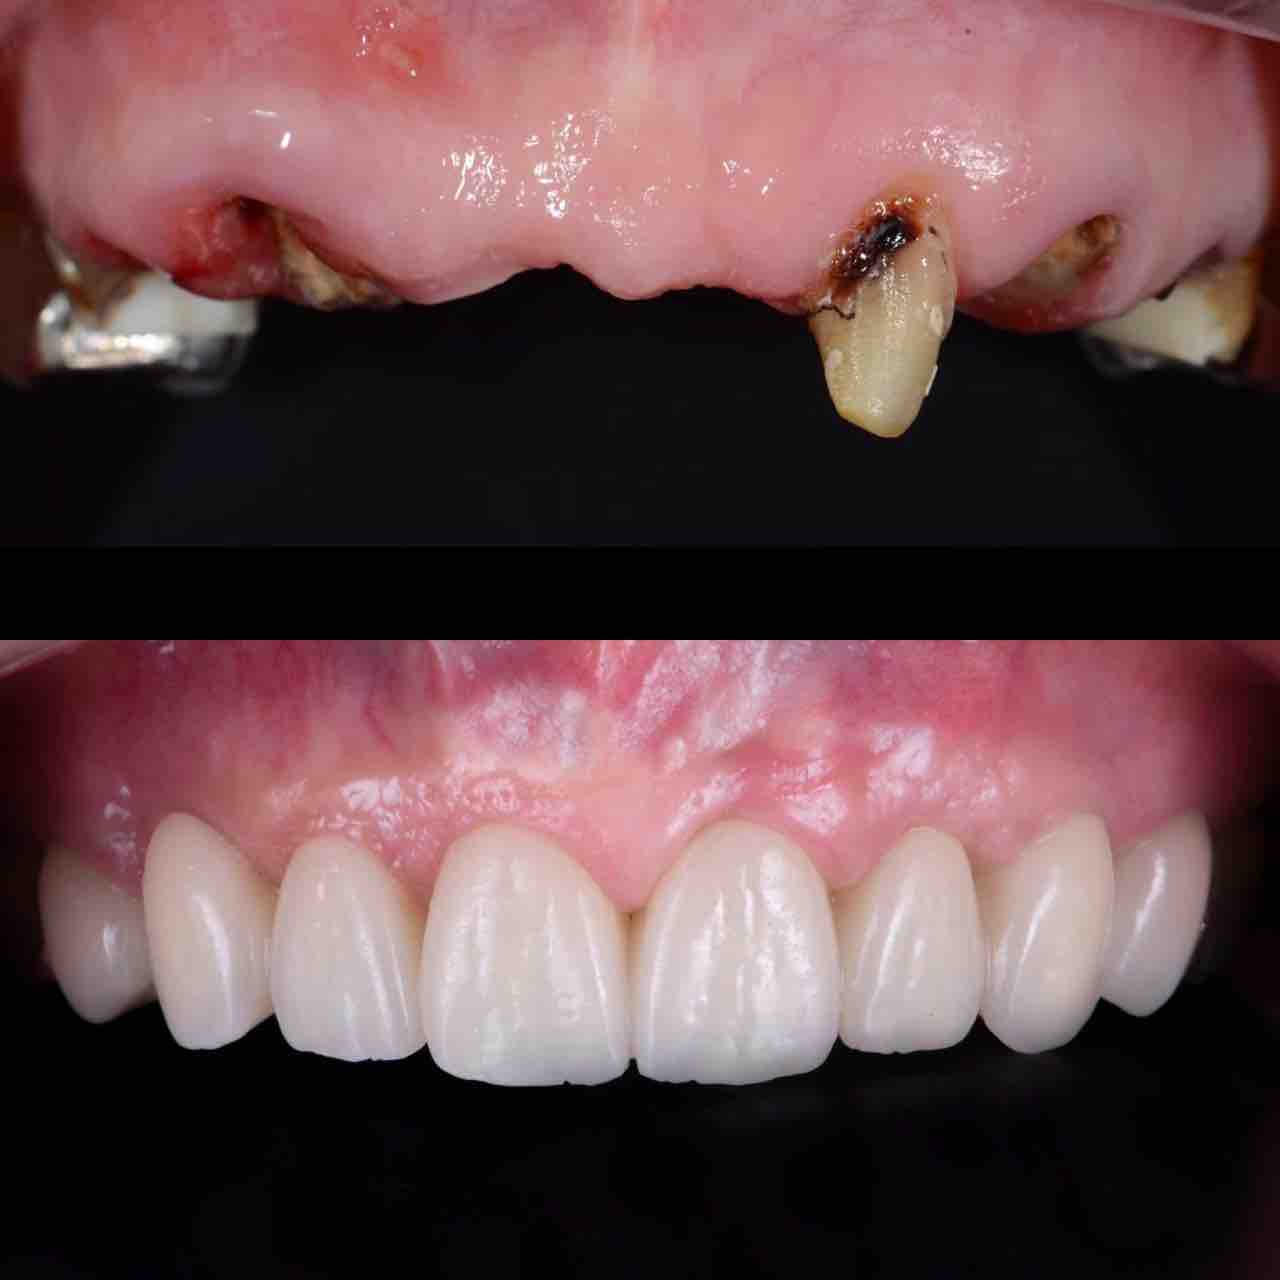

¥¤¥ó¥¹¥¿¥°¥é¥à¤ËºÜ¤»¤Æ¤¤¤ëÅö±¡¤Î¾ÉÎã¤Ç¤¹